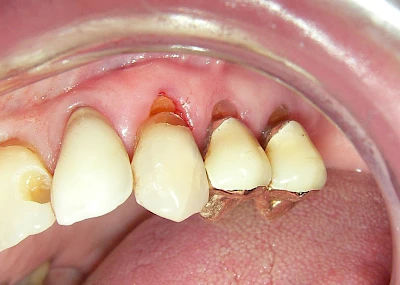

Keilförmiger Defekt

Eine Sonderform sind sogenannte keilförmige Defekte im Bereich der Zahnhälse. Hier geht man davon aus, dass Knirschen und Pressen in Kombination mit falschen Putzgewohnheiten (zu hoher Putzdruck, Verwendung von Zahnpasta mit hohen Abrasionswerten) eine Rolle spielen.